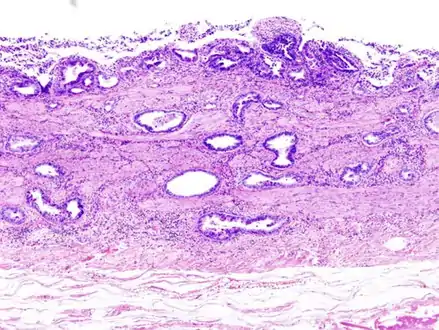

Gallbladder adenocarcinoma lymphatic invasion histopathology

Incidentally discovered gallbladder cancer (adenocarcinoma) following a cholecystectomy.